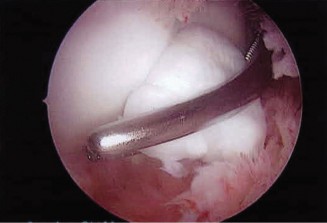

The patient undergoes conservative management consisting of rest, anti-inflammatory medications, and physical therapy. After six months, he is still not able to return to play and has progressively worsening symptoms with attempted throwing. He has a moderate elbow effusion as well as a 20-degree flexion contracture. An elbow MRI arthrogram is obtained and shown (Fig. 2–112). He elects to proceed with elbow arthroscopy. Intraoperative arthroscopic images are shown (Figs. 2–113 and 2–114).

Figure 2–112

Figure 2–113

Figure 2–114

Which of the following is the most commonly reported complication of elbow arthroscopy?

- Contracture

- Compartment syndrome

- Septic joint

- Neuropraxia

- Vessel injury

Discussion

The correct answer is (D). The overall reported rate of transient and permanent complications after elbow arthroscopy is around 10% and is much higher than the rate after knee and shoulder arthroscopy (1–2%). The overall most commonly reported complication is prolonged drainage or erythema around portal sites. The lateral portal sites are susceptible to this issue as the joint is relatively subcutaneous in this area, and there is scant tissue to act as a barrier. Deep infection, while being the most serious postoperative complication, is relatively rare (0.8%). In one series, the rate of transient neurological injuries was found to be 2%. These result from compression, local anesthetic injection, and direct trauma. A thorough understanding of the neurovascular anatomy of the elbow is crucial to achieve proper portal placement. Loss of elbow motion was reported in approximately 1% of cases and is usually minor (less than 20 degrees). Objectives: Did you learn...? Recognize the clinical and radiographic presentation of elbow osteochondritis dissecans?